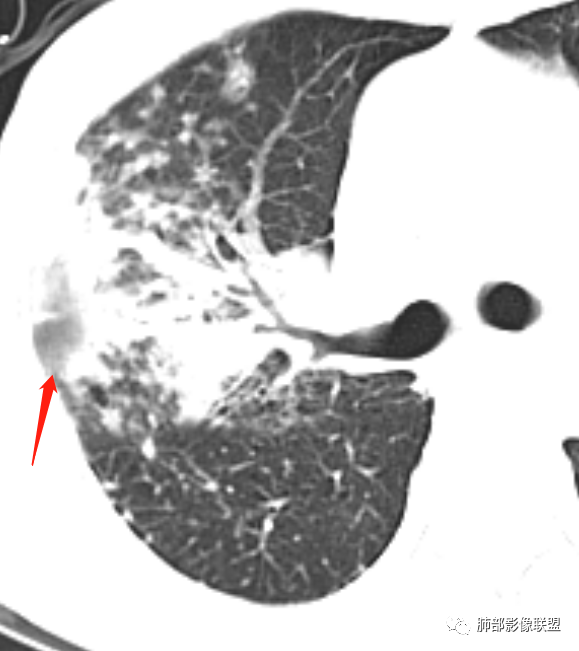

支气管血管束是增厚的,多发病灶及纤维灶,有钙化及纵隔钙化淋巴结,树芽征,支持结核合并其他感染。

就这里不让人放心,是占位吗?支气管是截断的,没有凹陷或者突出阻断,阻断前稍扩张

患者老年女性,亚急性起病,主要症状表现为咳嗽、咳痰半月余,查体:双现呼吸音粗,双肺可闻及痰鸣音。胸部CT:双上肺胸膜下可见多发小叶实变影,双上肺可见多发小叶中心性结节及小叶间隔增厚,右上肺后段可见亚段性实变影,内见多发空洞,前段可见GGO及树芽征,后段局部支气管闭塞,肺门淋巴结肿大并钙化。病灶整体:有气道、间质播散,一元论考虑肺结核合并支气管结核可能性大,建议好好查痰;这样病灶:明显实变+空洞+气道播散,若是结核,痰涂片找到抗酸杆菌应该没问题。建议支气管镜检查助诊,了解有无支气管结核及合并腺癌的可能。

1、树芽征

4、反晕征

1.双肺片状影、大小不等斑片影、结节影、树芽等,病灶密度偏高多钙化。

2.病灶上肺为主,胸膜下分布为主。双肺病灶明显不对称,右肺块状影较大。

3.纤维条索影广泛杂乱、牵拉,横向分布为主,这点给人也印象很深!

1.胸膜下为主,簇状分布,大小不等,新旧不等,树芽,密度偏高等等都结核病变影像学特点。